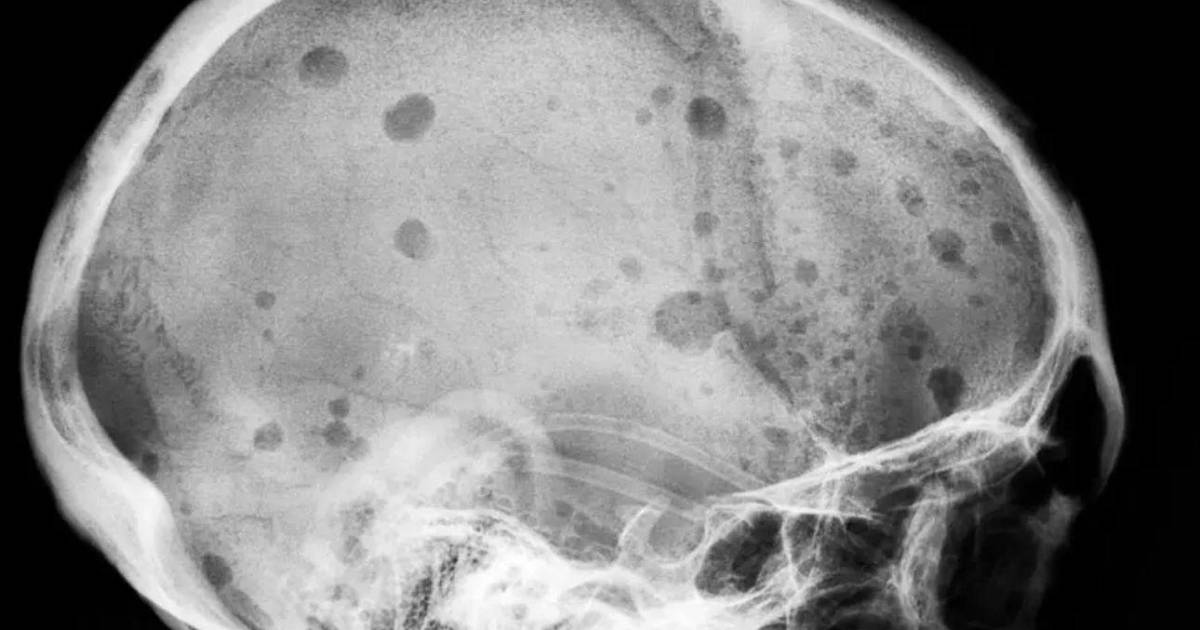

Las personas que desarrollan mieloma múltiple enfrentan una enfermedad que deteriora los huesos, afirmó Carl June, de la Universidad de Pensilvania. June ha visto a pacientes que perdieron 15 centímetros de estatura. “Es una muerte muy horrible”, declaró June.